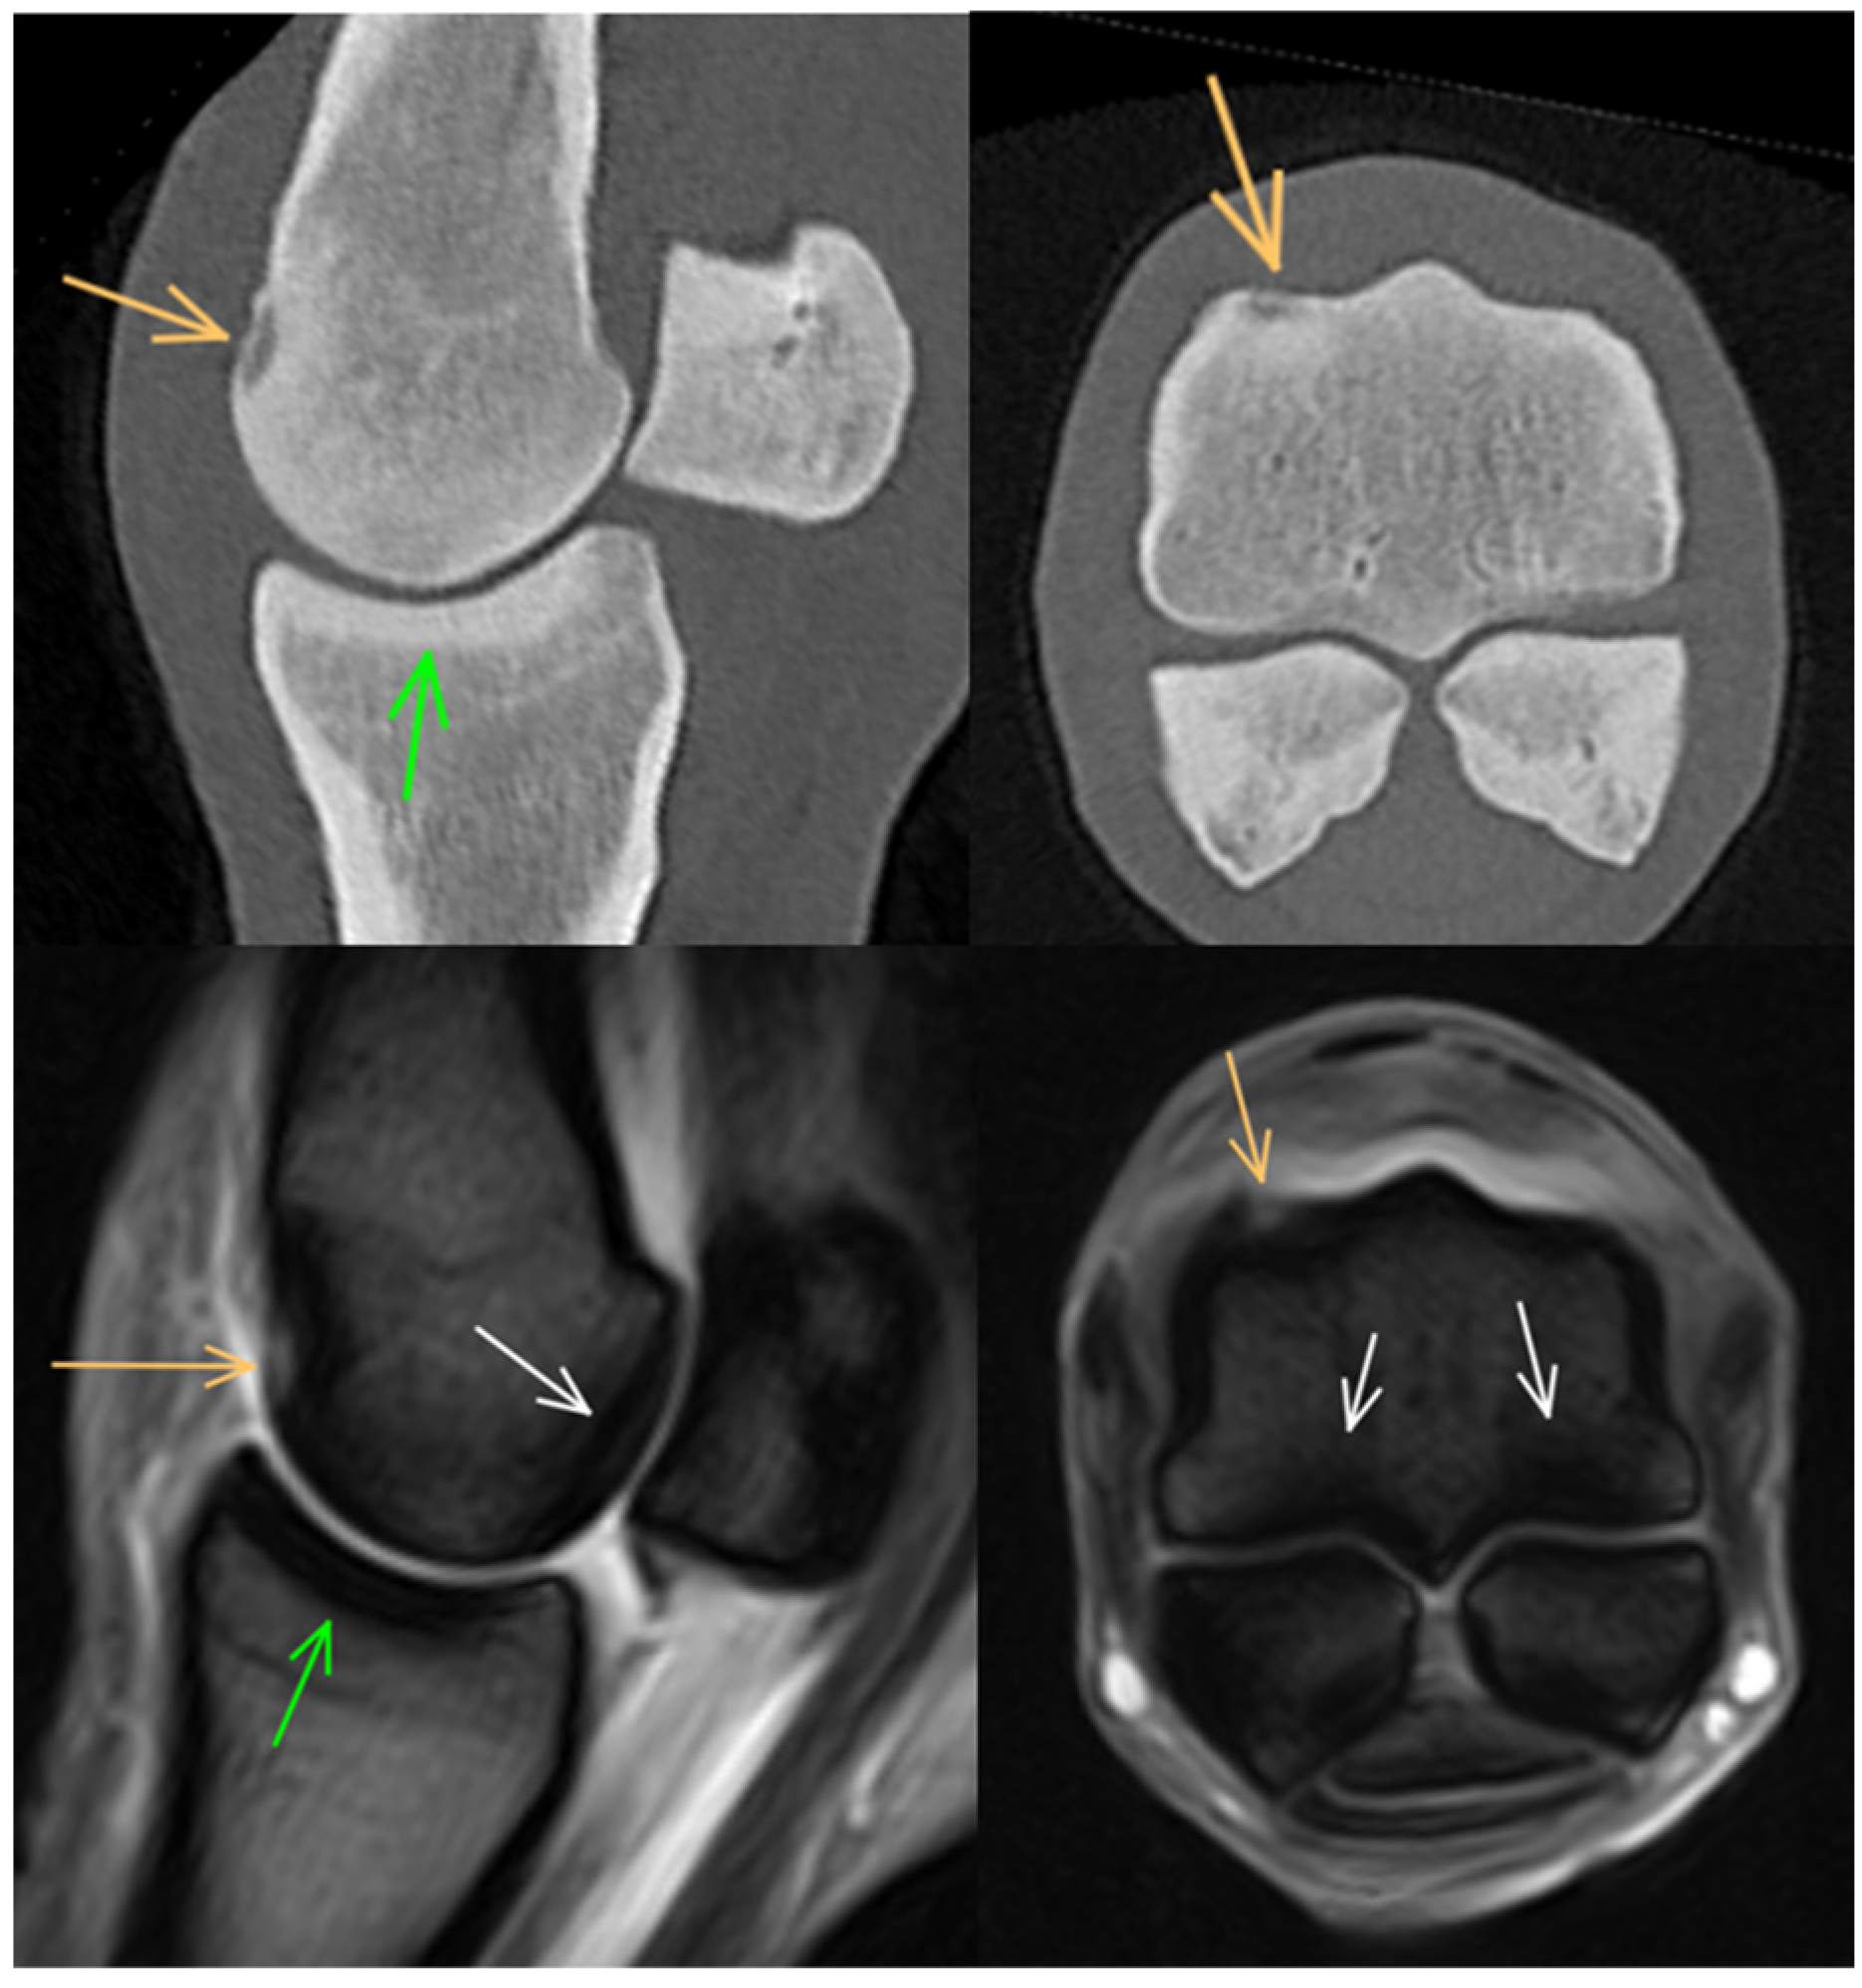

3.1. Third Metacarpal Bone

3.2. Proximal Phalanx

3.3. Proximal Sesamoid Bones

3.4. Soft Tissues